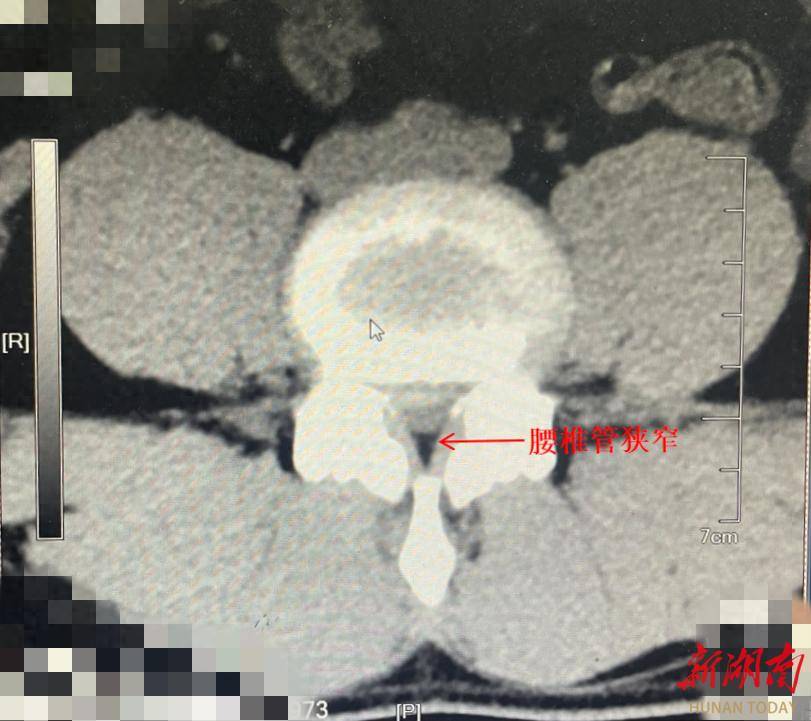

大众卫生报·新湖南客户端5月13日讯(通讯员 张文霞 王桂香)湖南湘西34岁的郑先生正处于身强力壮的年纪,但他却被反复发作的腰痛困扰了17年。久病不仅未能自愈,反而越拖越严重,发展到了无法正常行走的地